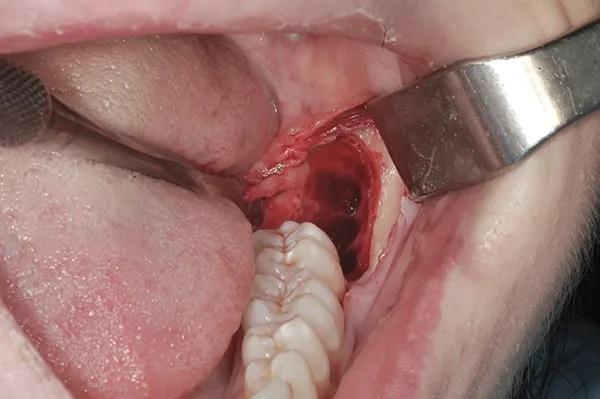

Пациенту было рекомендовано перед операцией использовать 0,12%-ный раствор хлоргексидина глюконата для полоскания рта. Была проведена местная анестезия с помощью блокады НАН и длинного щечного нерва с использованием двух картриджей с 3%-ным мепивакаином и сосудосуживающим средством, и была подтверждена глубокая местная анестезия. Был сделан разрез борозды от дистальной части зуба 3.6 до дистальной части зуба 3.7, при этом разрез гребня продолжался кзади от восходящей ветви нижней челюсти, и был поднят полнослойный конвертный лоскут. В частности, дистальный разрез продолжался под углом 45 градусов от дистобуккального бугорка зуба 3.7 до ветви нижней челюсти (Фото 3).

Фото 3: Окклюзионный вид “двойного зуба”.